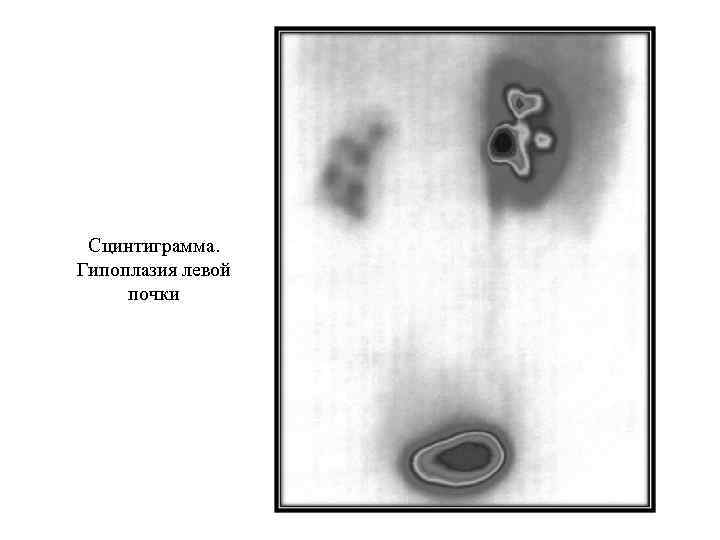

Сцинтиграмма. Гипоплазия левой почки

Сцинтиграмма. Гипоплазия левой почки